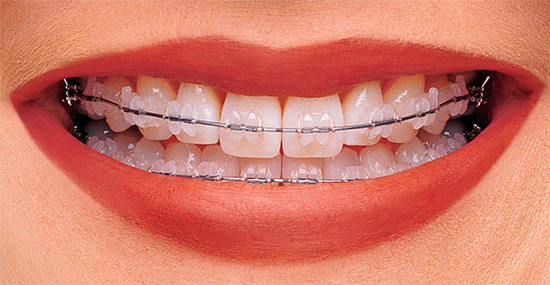

- Le parentesi graffe di plastica sono più estetiche, poiché coincidono con il colore naturale dei denti. Tra gli svantaggi: sono dipinti con cibo e non durano come il metallo, il che a volte costringe il medico a incollare una nuova staffa a causa del fallimento dell'originale e questo è un costo aggiuntivo per il paziente.

- Bretelle in ceramica - non visibili sui denti, più resistenti di quelle in plastica. Tra gli svantaggi - a causa dell'elevato grado di attrito dell'arco nel castello, il tempo di trattamento totale aumenta. Il costo di tali apparecchi è superiore a quello del metallo e della plastica.